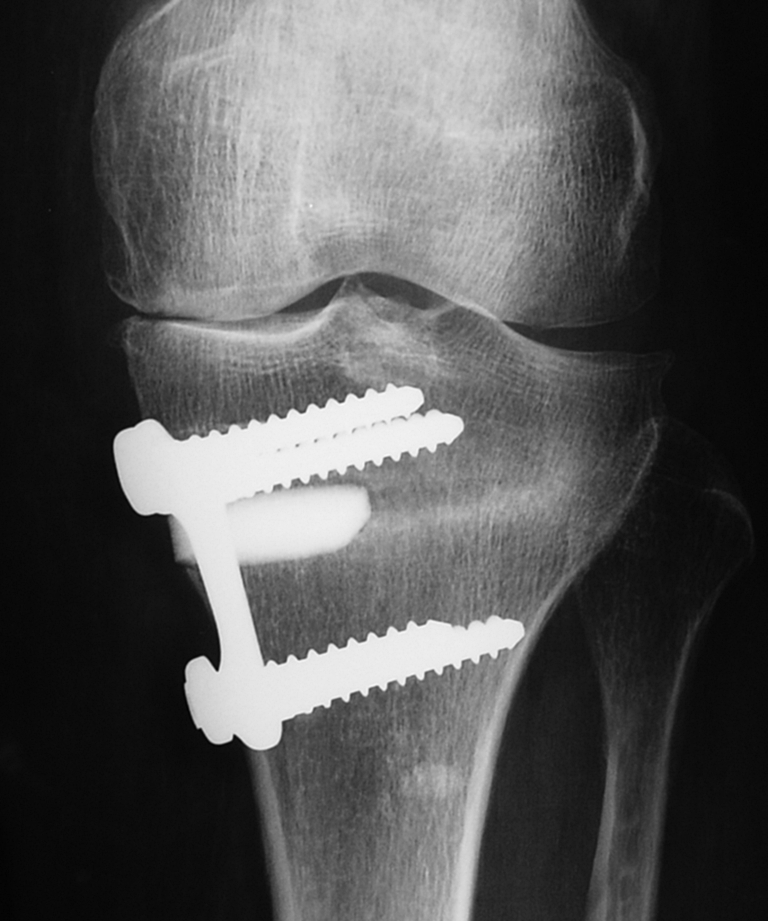

Fig. 5.

Radiological result of an high tibial osteotomy (HTO) (three-month follow-up)